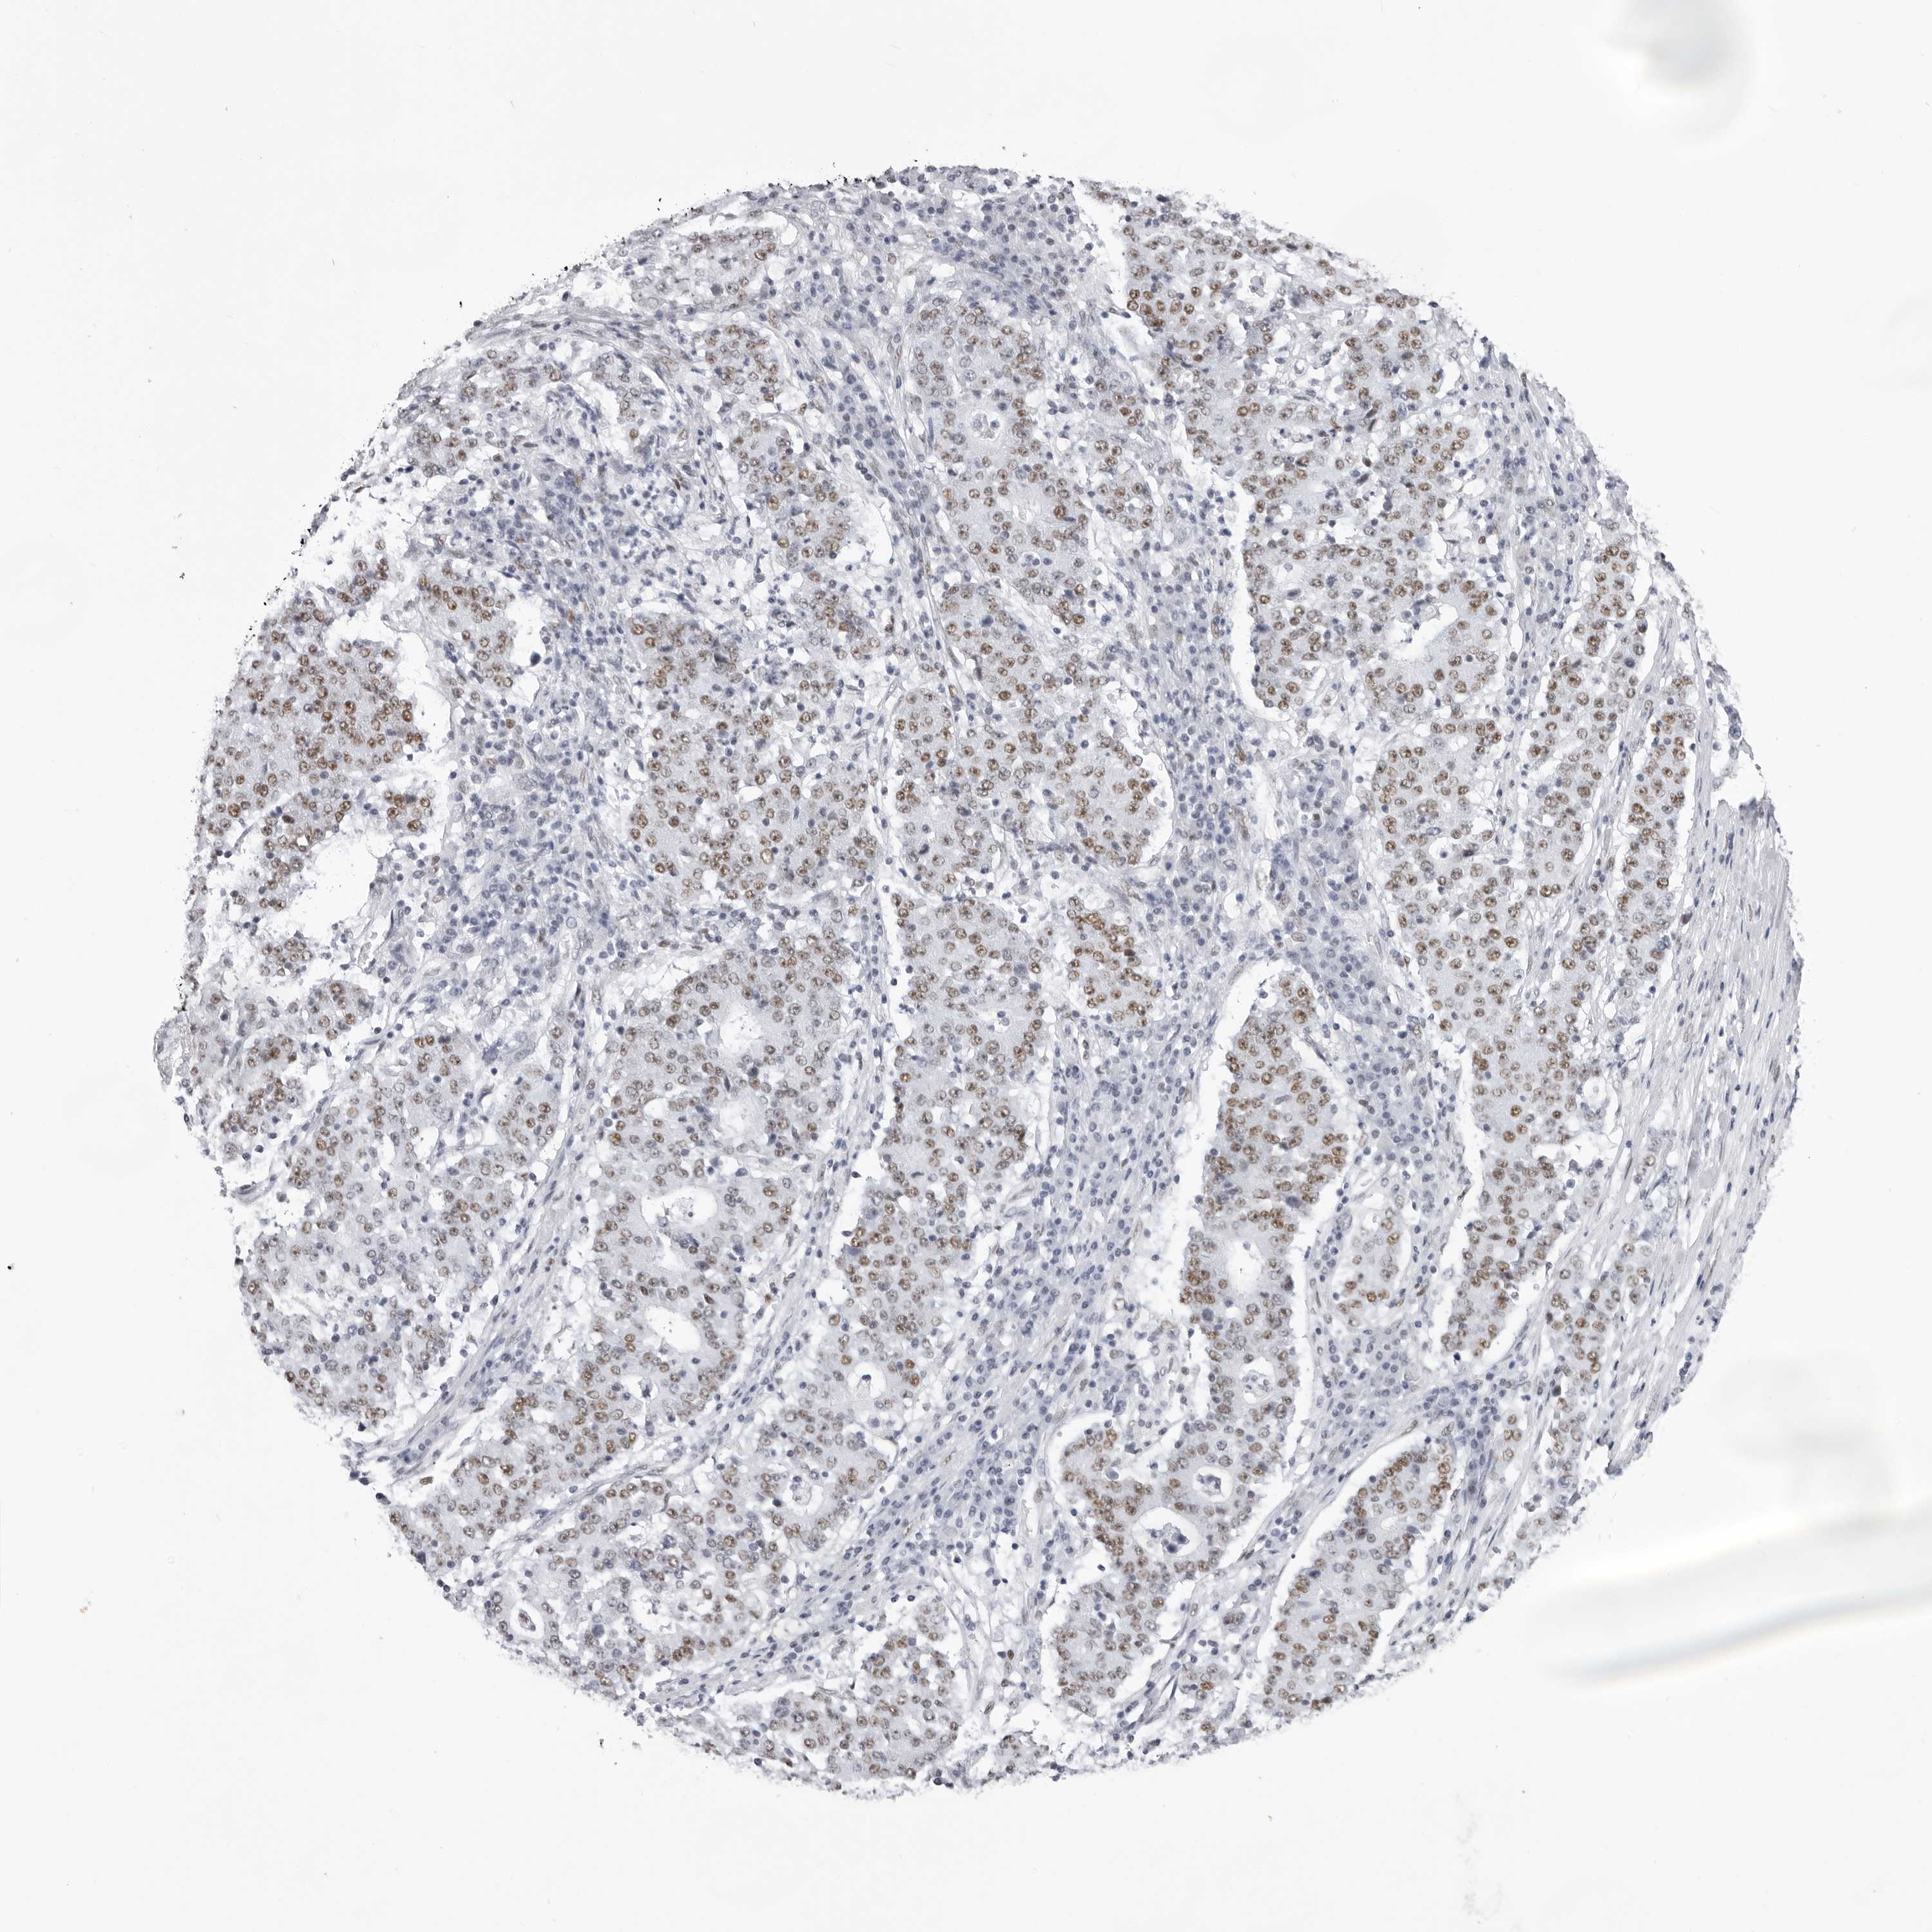

STOMACH CANCER - Protein expressioni

A mouse-over function shows sample information and annotation data. Click on an image to view it in a full screen mode. Samples can be filtered based on level of antibody staining by selecting one or several of the following categories: high, medium, low and not detected. The assay and annotation is described here.

Antibody stainingi

Antibody staining in the annotated cell types in the current human tissue is reported as not detected, low, medium, or high, based on conventional immunohistochemistry profiling in selected tissues. This score is based on the combination of the staining intensity and fraction of stained cells.

Each image is clickable and will lead to virtual microscopy that enables deeper exploration of all samples and also displays staining intensity scores, fraction scores and subcellular localization as well as patient and tissue information for each sample.

Antibody HPA027815

Staining

High

Medium

Low

Not detected

Intensity

Strong

Moderate

Weak

Negative

Quantity

>75%

75%-25%

<25%

None

Location

Nuclear

Cytoplasmic/membranous

Cytoplasmic/membranous,nuclear

Adenocarcinoma, NOS